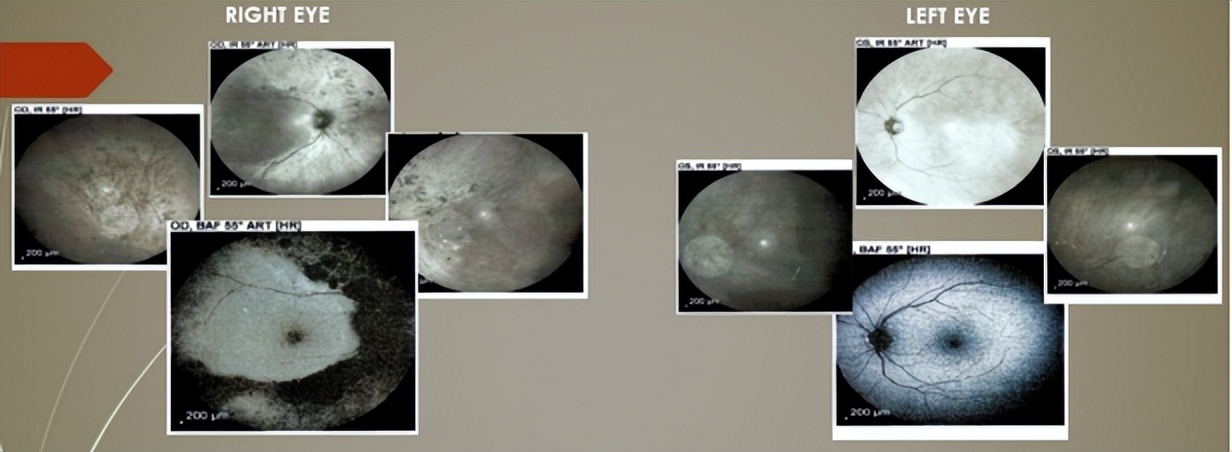

红外眼底成像(IR)&眼底自发荧光扫描(BAF):OD:IR色素团块(周边视网膜中),BAF显示上下血管弓外RPE层自发荧光缺失;OS:IR和BAF无病理特征或视网膜变性体征。